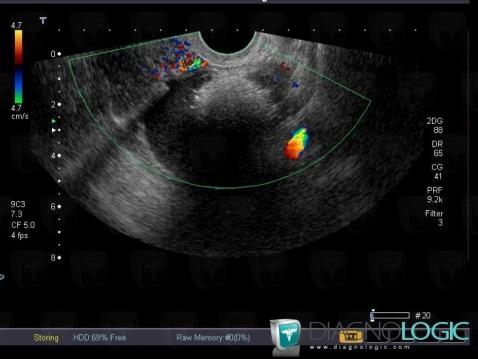

Teratoma, Adnexa / Ovary fallopian tube, Pelvis / Perineum, US

Here is the specific information in the key image above:

- Diagnosis Teratoma (link to Dermoid cyst), Location(s) Adnexa / Ovary fallopian tube, with gamuts Complex adnexal massPelvis / Perineum, with gamuts Complex pelvic mass